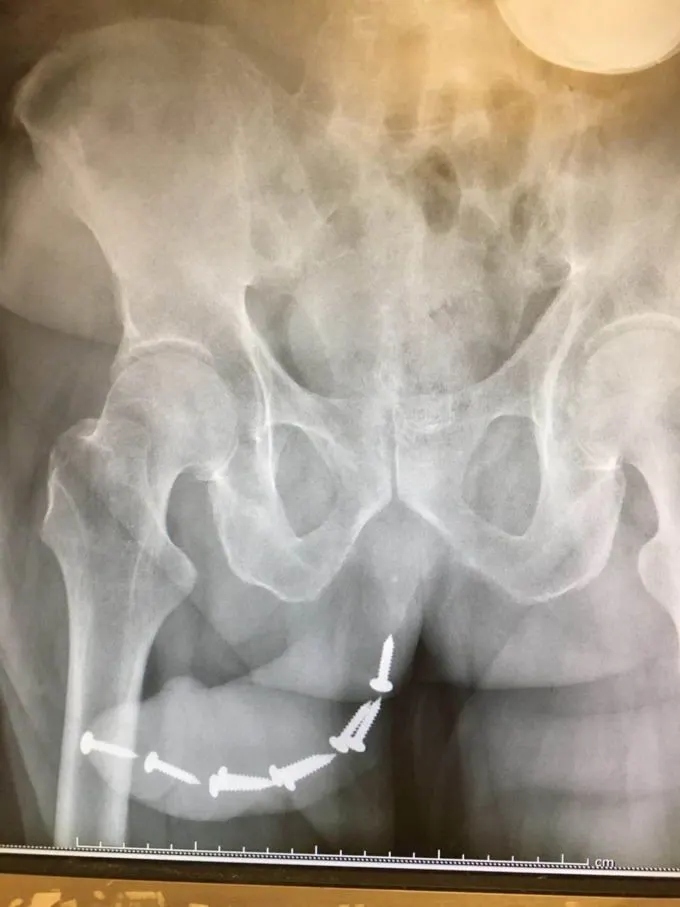

11.ภาพเอ็กซเรย์ของชายที่มีตะปูกว่า 12 อันบริเวณทวาร